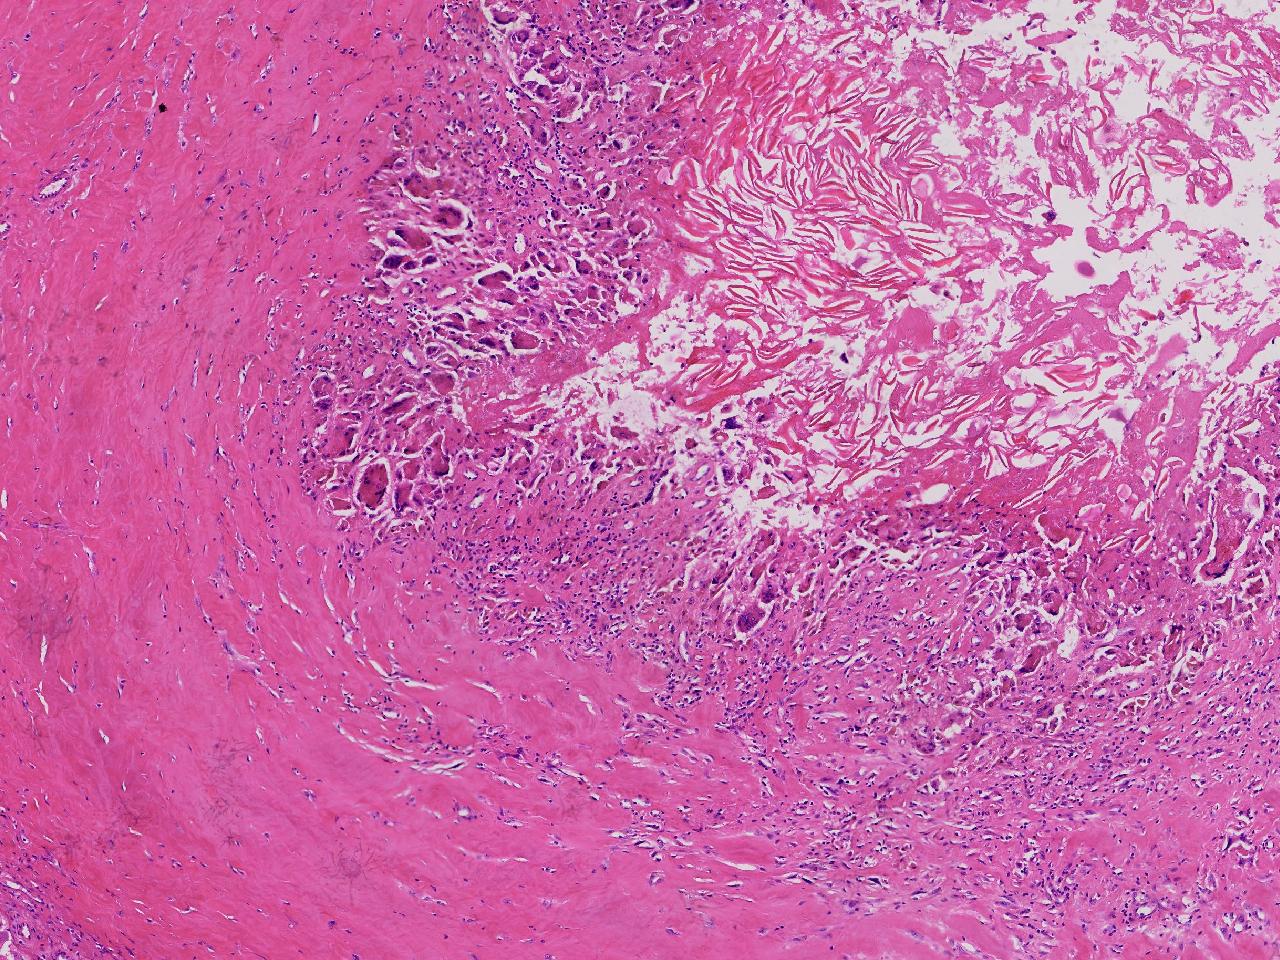

皮样/表皮样囊肿伴周边异物巨细胞反应?

右侧臀部皮下肿物10余年,渐增大,无破溃,无疼痛。

右侧臀部皮下肿物

囊性肿物一个,直径2.5厘米,肿物位于皮下。

异物肉芽肿性炎?

表皮样囊肿伴异物肉芽肿性炎。